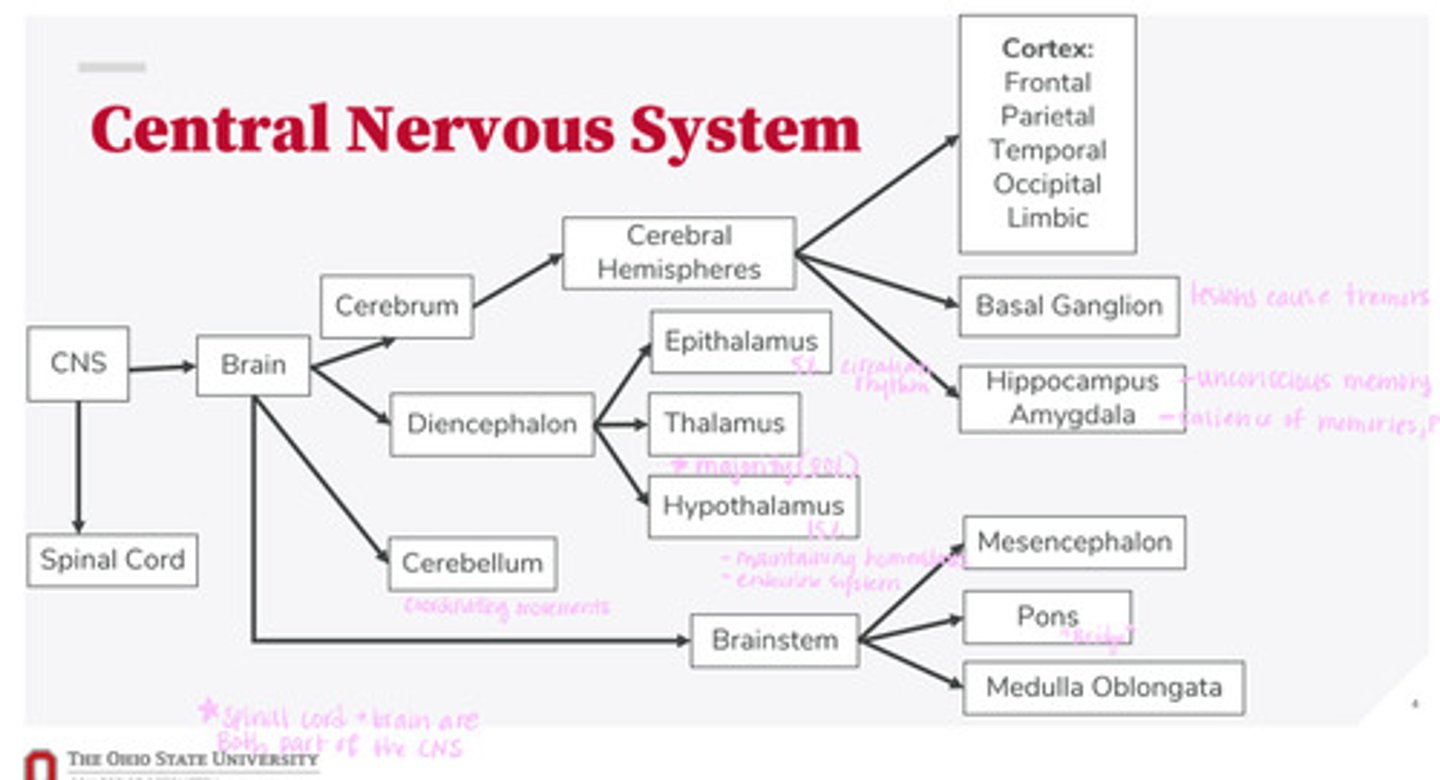

-brain

-spinal cord

What are the 2 divisions of the CNS?

-cerebrum

-diencephalon

-cerebellum

-brainstem

What are the 4 divisions of the brain?

-epithalamus

-thalamus

-hypothalamus

What are the 3 divisions of the diencephalon?

-mesencephalon

-pons

-medulla oblongata

What are the 3 divisions of the brainstem?

-cortex

-basal ganglion

-hippocampus

-amygdala

What are the divisions of the cerebral hemispheres?

-frontal lobe

-parietal lobe

-temporal lobe

-occipital lobe

-limbic system

What are the divisions of the cortex?

coordinating movements

What is the function of the cerebellum?

thalamus

A majority of signals from the diencephalon flow into where?

circadian rhythm

What is the function of the epithalamus?

-maintaining homeostasis

-endocrine system function

What is the function of the hypothalamus?

tremors

Lesions on the basal ganglion cause what?

hippocampus

What part of the brain is in control of unconscious memory?

amygdala

What part of the brain is in control of the salience of memories (PTSD)?

The bridge between the mesencephalon and the medulla oblongata

What is the function of the pons?